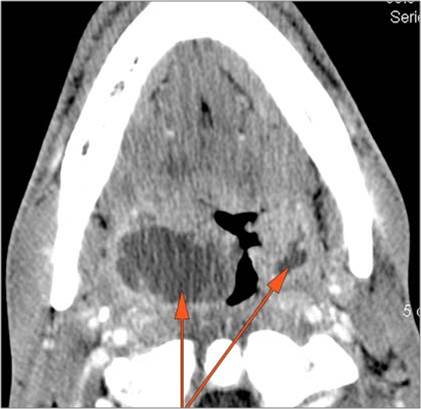

There is edema/abscess tonsillar or otherwise or likely suppurative retropharyngeal adenitis involving the oropharynx or adjacent deep tissue spaces. |

Yes | NA |

|

There is edema/abscess within or surrounding the buccal space, masticator space, floor of the mouth, submandibular space or the adjacent superficial fascia or subcutaneous fat and skin. |

There is edema/abscess arising from the hypopharynx, larynx, thyroid gland or trachea. |

There is edema/abscess within the adjacent deep neck, and/or retropharyngeal space. |